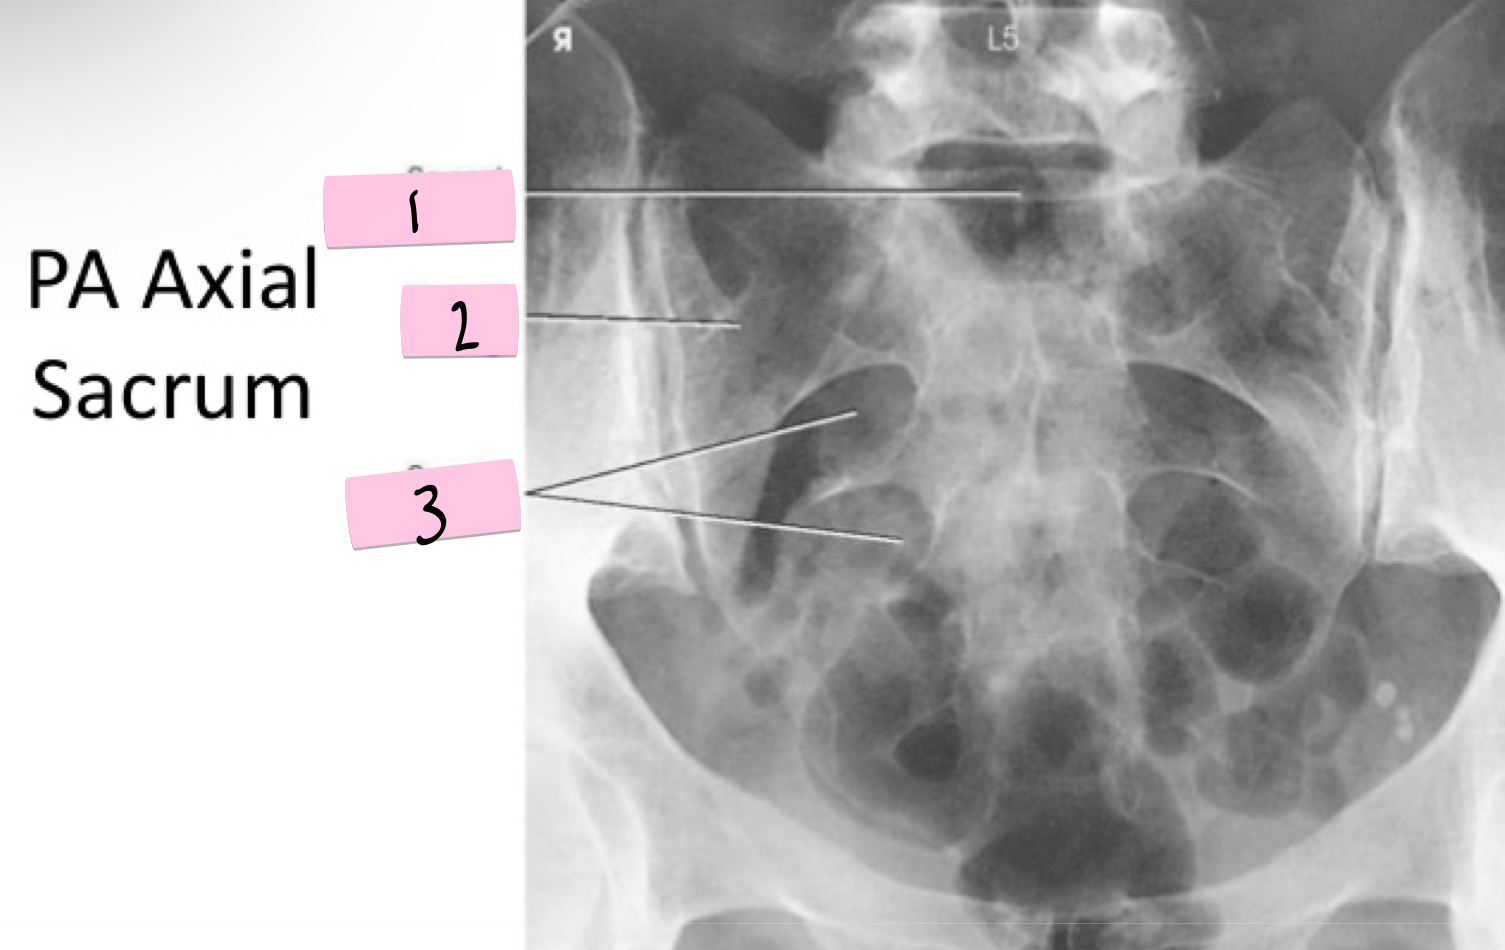

What is 1 pointing to?

Sacral promontory

What is 2 pointing to?

Sacral wing

What is 3 pointing to?

Sacral foramina